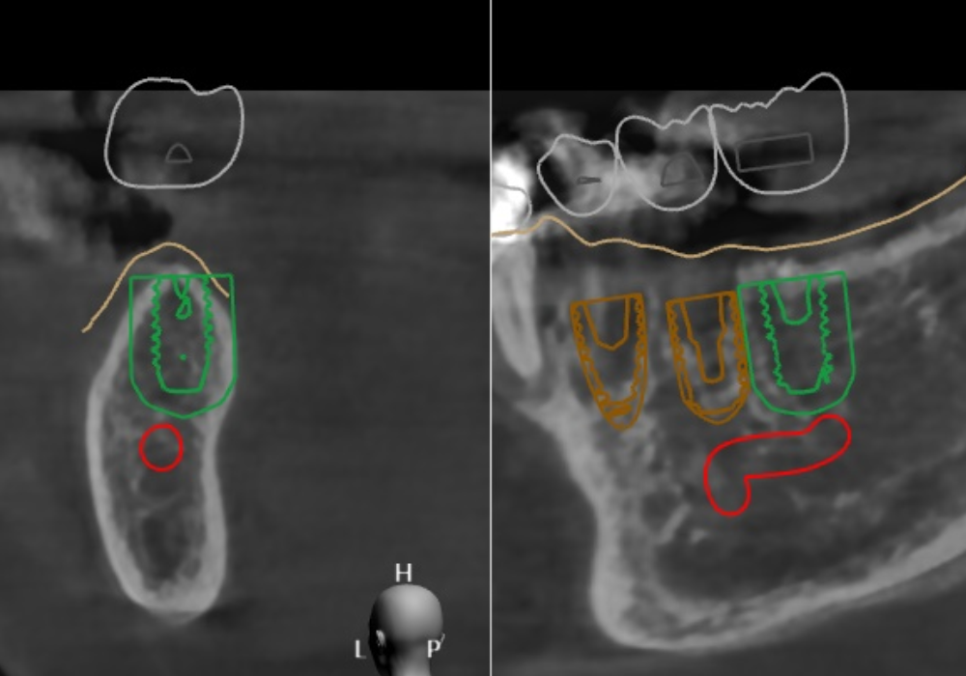

반면 디지털 가이드(네비게이션) 방식은

3D CT와 구강 스캐너 데이터를 결합해

컴퓨터상에서 미리 모의 수술을 해보는 방식이에요.

이를 통해 임플란트가 들어갈

최적의 경로를 찾고,

그 길을 그대로 안내해주는

서지컬 가이드라는 맞춤형 틀을 제작하게 됩니다.

저희는 디지털 시스템을 활용하여

3D 데이터를 통해 신경의 위치를 미리 파악하고,

잇몸뼈가 가장 튼튼한 곳을 골라

최적의 각도로 설계를 마쳤습니다.